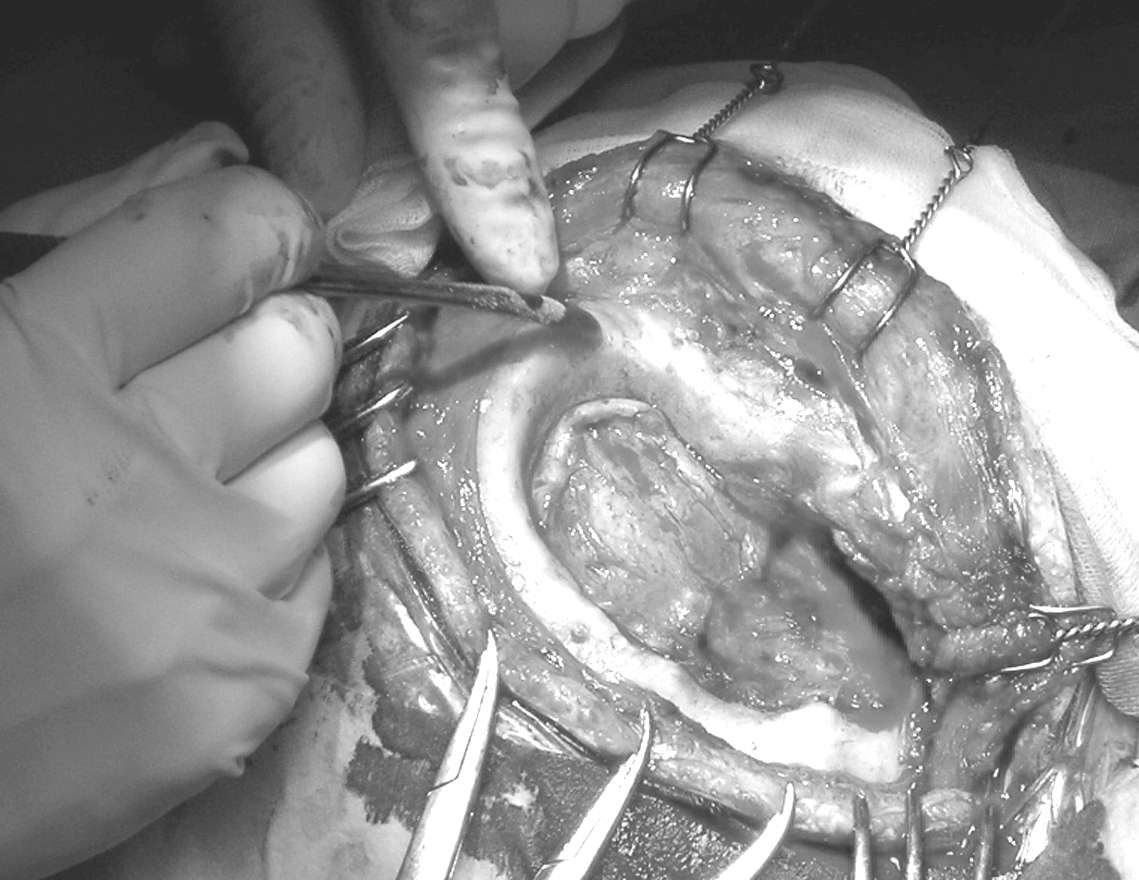

LE SOSPENSIONI

Le sospensioni durali centrali sono, ovviamente, sempre consigliate.

Quelle ai bordi craniectomici sono indispensabili se si tratta di una demolizione-ricostruzione in quanto la dura ai margini può risultare ampiamente scollata.

Solitamente non sono necessarie le sospensioni durali laterali nei casi di riaperture di precedenti craniectomie in quanto le aderenze fibrotiche sui margini ne impediscono lo scollamento, scongiurando il verificarsi di un ematoma extradurale post-chirurgico.

Un cenno su una particolare problematica va fatto quando si è di fronte ad ampie introflessioni durali per mancanza di sostanza encefalica sottostante. In questi casi bisogna fare molta attenzione nel sollevamento delle sospensioni centrali. Se la dura viene troppo trazionata si possono realizzare delle lacerazioni parenchimali, nel caso di corteccia aderente alla dura, o la rottura delle vene a ponte con conseguente ematoma sottodurale.

Anche se non si può escludere a priori è ben difficile che ci si trovi nella necessità, nelle amplissime craniectomie, di eseguire una plastica durale al fine di ampliarne la superficie e permettere un ottimale sollevamento verso il tavolato in idrossiapatite.